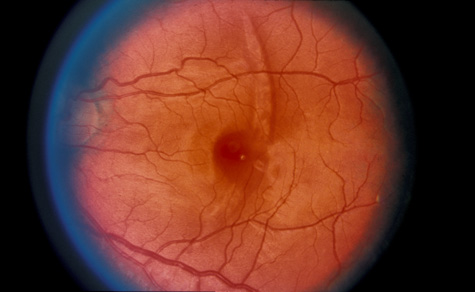

Fig. 9. Commotio retinae in the macula (Berlin's edema). The visual acuity was 20/25 at the time of the photograph and later improved to 20/15.